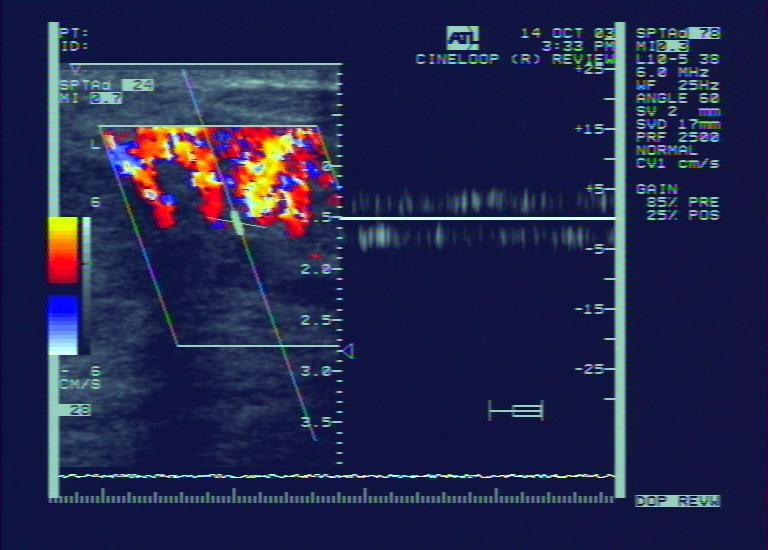

问题 乳腺癌CDFI特点是?(?)

选项 A.无血流信号 B.彩色血流不丰富,血管数目少 C.彩色血流丰富,呈高速低阻血流 D.彩色血流丰富,呈高速高阻血流 E.彩色血流不丰富,呈高速低阻血流

答案 D